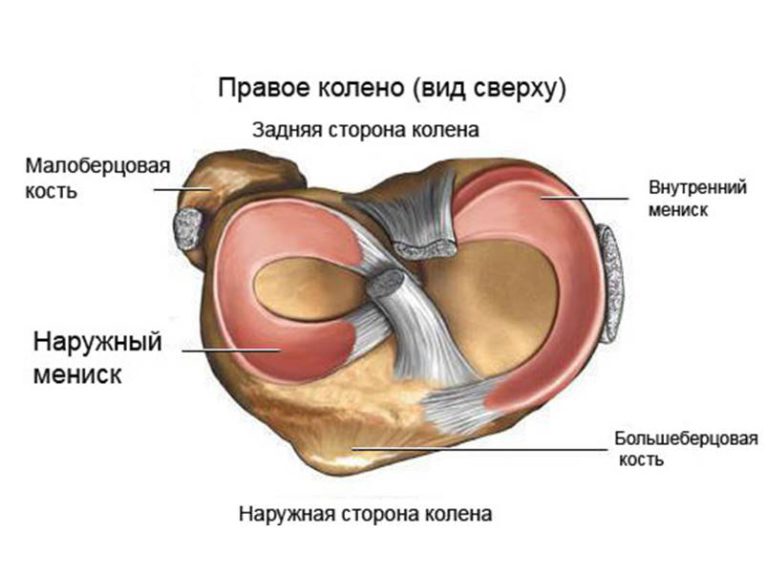

Причины и лечение травм коленного сустава